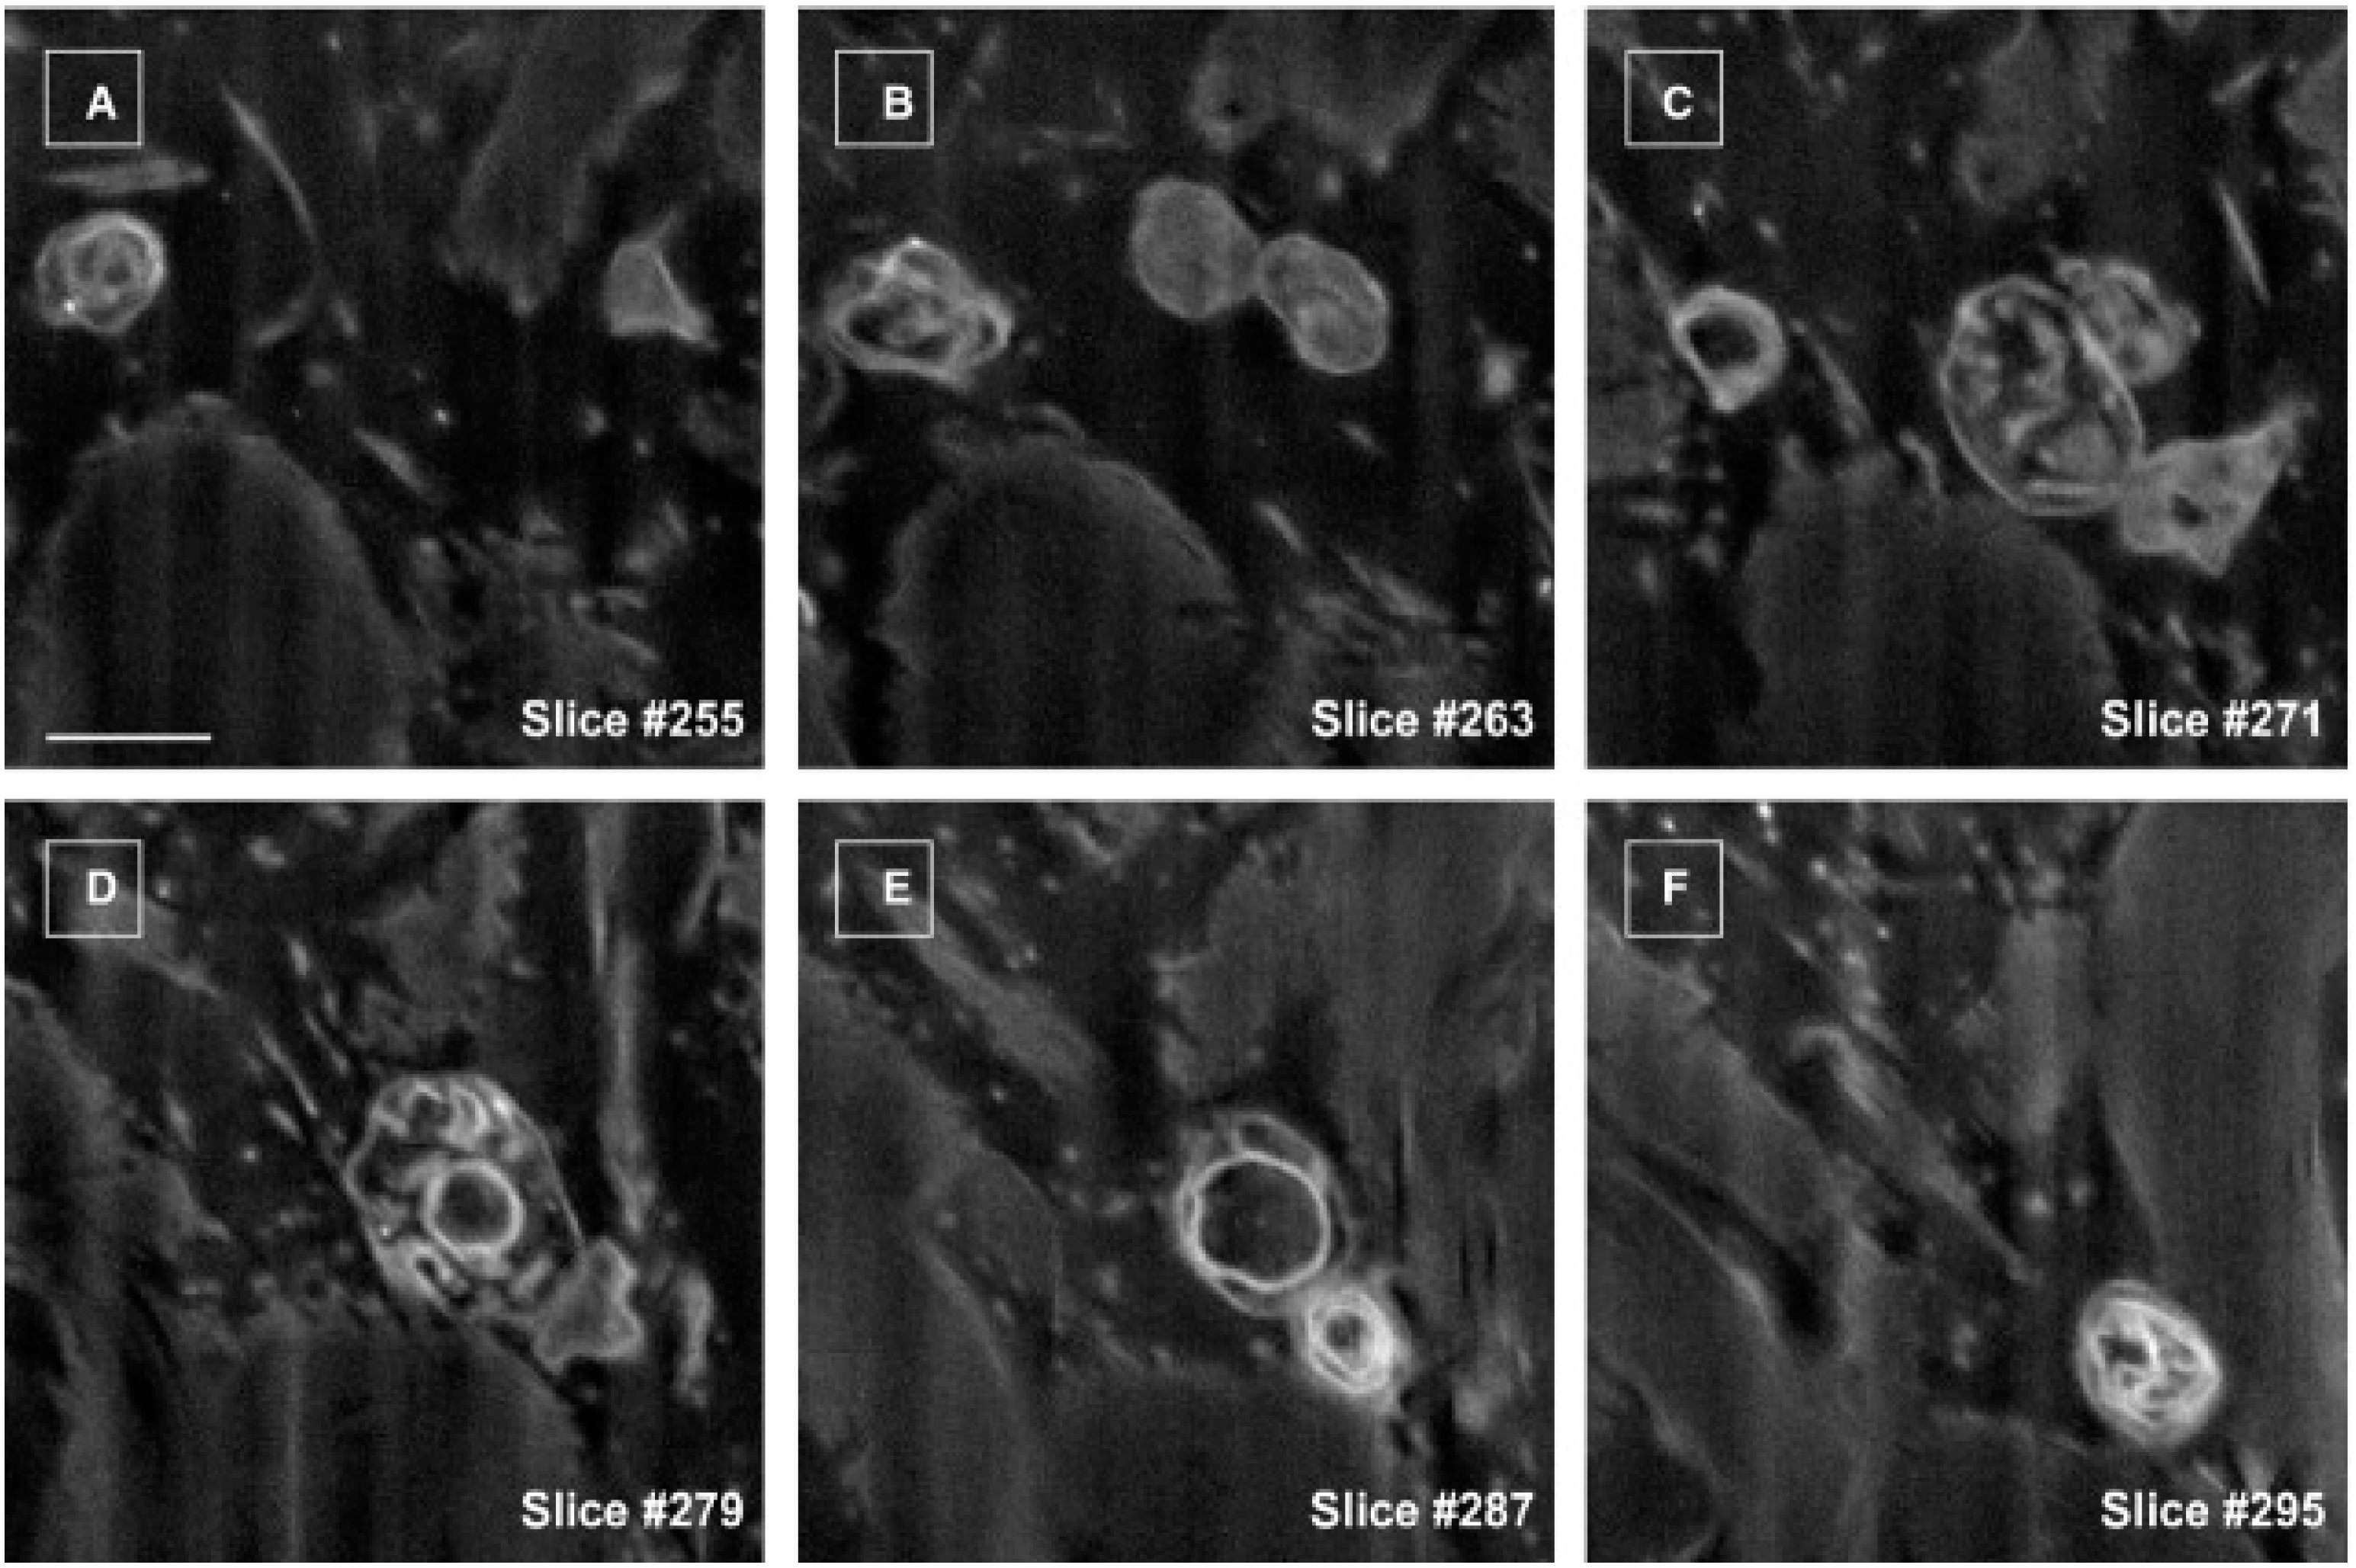

- Cretoiu, D.; Hummel, E.; Zimmermann, H.; Gherghiceanu, M.; Popescu, L.M. Human cardiac telocytes: 3D imaging by fib-sem tomography. J. Cell. Mol. Med. 2014, 18, 2157–2164. [Google Scholar] [CrossRef] [PubMed]

- Cretoiu, D.; Gherghiceanu, M.; Hummel, E.; Zimmermann, H.; Simionescu, O.; Popescu, L.M. Fib-sem tomography of human skin telocytes and their extracellular vesicles. J. Cell. Mol. Med. 2015, 19, 714–722. [Google Scholar] [CrossRef] [PubMed]